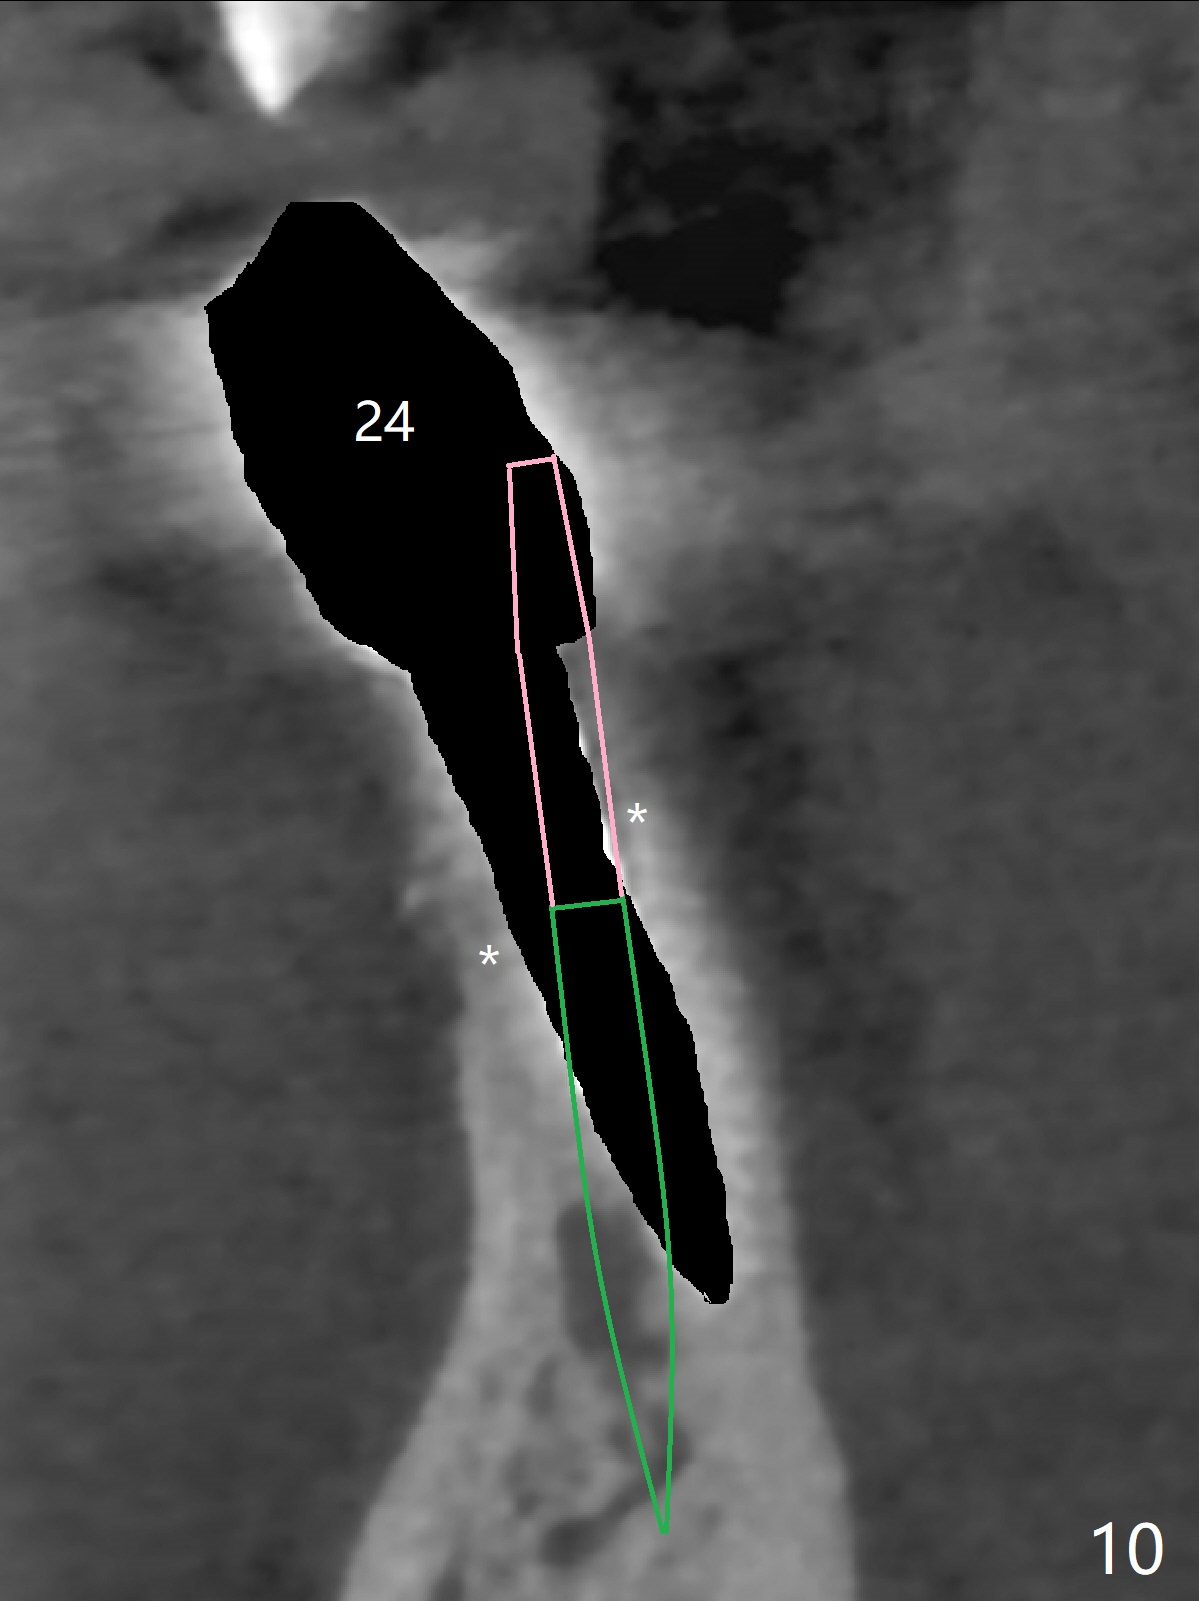

The fenetration found buccal to #25 two months post cementation persists, although asymptomatic, 4 months post cementation. Blood is drawn for PRF. In fact the implants at #24 and 25 are exposed buccal; there is limited amount of the buccal bone (Fig.1 *). After granulation tissue removal, Titanium brush is used to clean the implant threads. Allograft and Osteogen are mixed with PRF liquid to form gel, which is placed over the exposed implant threads. The bone graft is covered with a piece of PRF membrane and a piece of collagen membrane (Fig.2 C). Immediately postop PA (Fig.3) and CBCT (Fig.4) show that the implants have sufficient clearance between them. The implant thread exposure is most likely due to failure to place the implants deep enough and the implants are slightly large relative to the ridge (Fig.5-8). If the bone graft does not heal, new type of 1-piece implants (Fig.9,10 (green) smaller in diameter, 2 or 2.5 mm ) with longer abutment (pink) will be placed subcrestal buccal with guide.